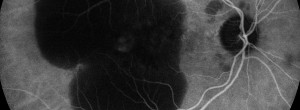

Update on Geographic Atrophy in Age-Related Macular Degeneration.